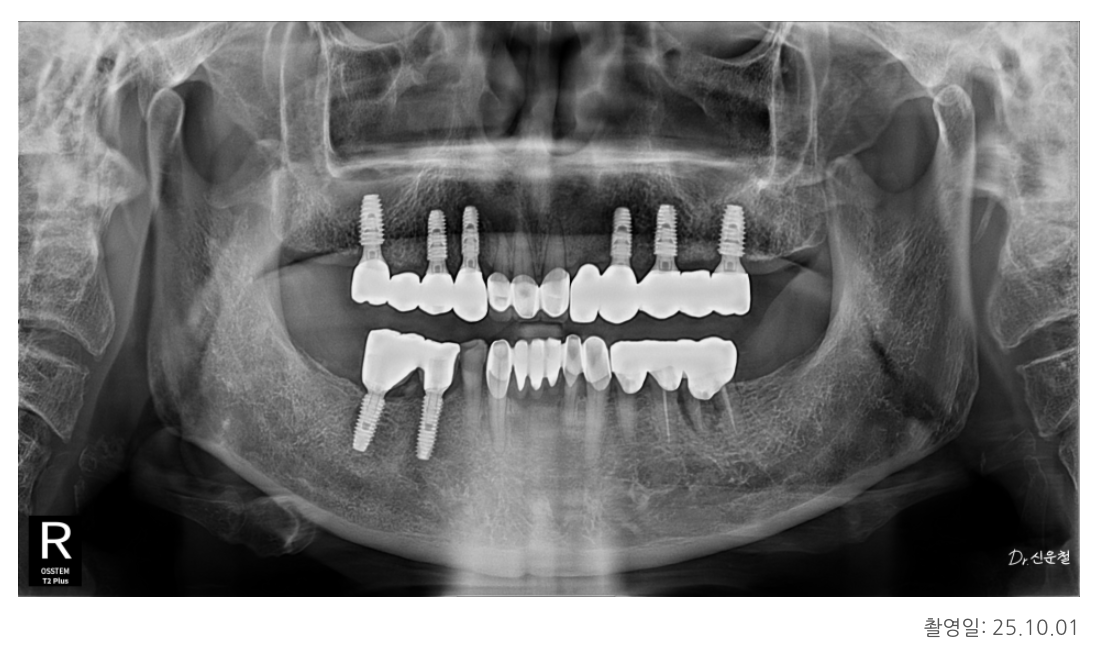

✔ 힘을 오래 버티는 ‘짧은 다리 구조’가 핵심

디에스다솜치과 임플란트에서는

“많이 심는 것”보다

오래 버티는 구조를 만드는 것을 원칙으로 합니다.

특히 위턱 뼈는 아래턱보다 부드럽고 힘을 받는 면적도 좁기 때문에

빠진 치아를 여러 개 한 줄로 길게 만들면

힘이 한쪽으로 쏠려 오래 버티기 어렵습니다.

그래서 우리는

임플란트 2개를 기둥으로 세우고

그 사이 치아 1개를 자연스럽게 연결하는 구조(다리 구조)를 선택했습니다.

이 방식은 수술 범위를 최소화하고

씹는 힘을 고르게 분산시키는 장점이 있습니다.

✔ 치료 방향: 총 6개의 임플란트로 기능 회복

치아 기능이 유지되는 아래턱의 범위를 기준으로

위턱 역시 좌우 6개 영역에서 맞춰 균형을 잡았습니다.